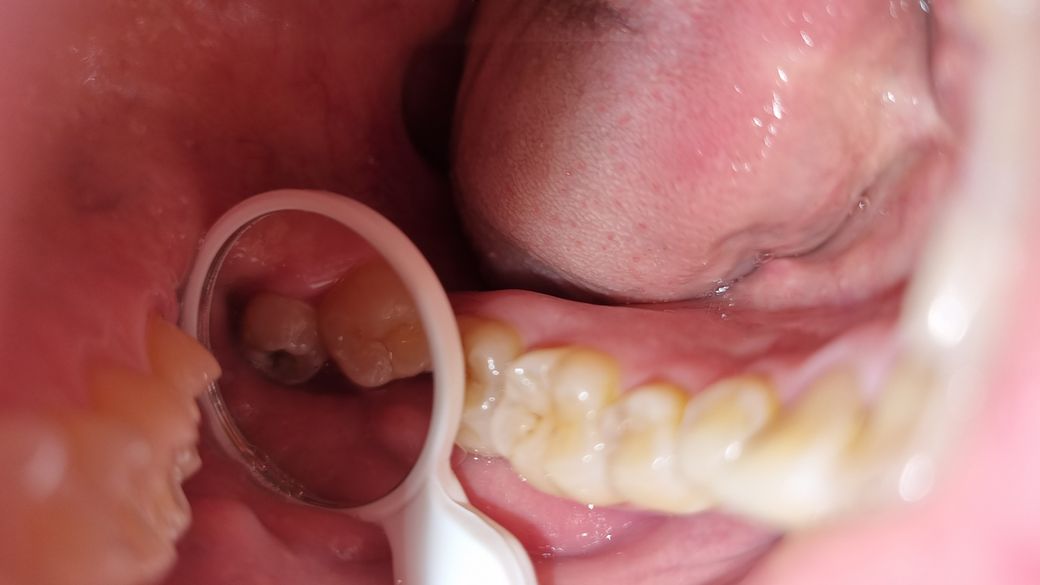

오른쪽 윗니에 사랑니 충치인가요?

오른쪽 윗에 이거 사랑니 맞나요? 충치생긴 건가요?

치과를 한 번도 안 가본 40대 입니다 치과 너무 무서워서 하루 8번이상 닦는데 사랑니가 있는줄 몰라서 제대로 안닦아서 그런지 충치생긴거 같은데요

• 1번 째 사진

사진을 보니 윗니 사랑니에 충치가 생겨있네요 저정도 충치는 정지되지않고 양치질이나 관리가 안 될 것으로 보이니 치과에 가서 발치하시는것이 나을 것 같습니다.

사진으로 봤을때 사랑니인것으로 보입니다.

또한, 사랑니에 충치가 꽤 진행된것으로 보입니다.

정확한것은 방사선사진을 봐야 알 수 있지만, 사진만으로 보면 사랑니를 빼는게 좋습니다.